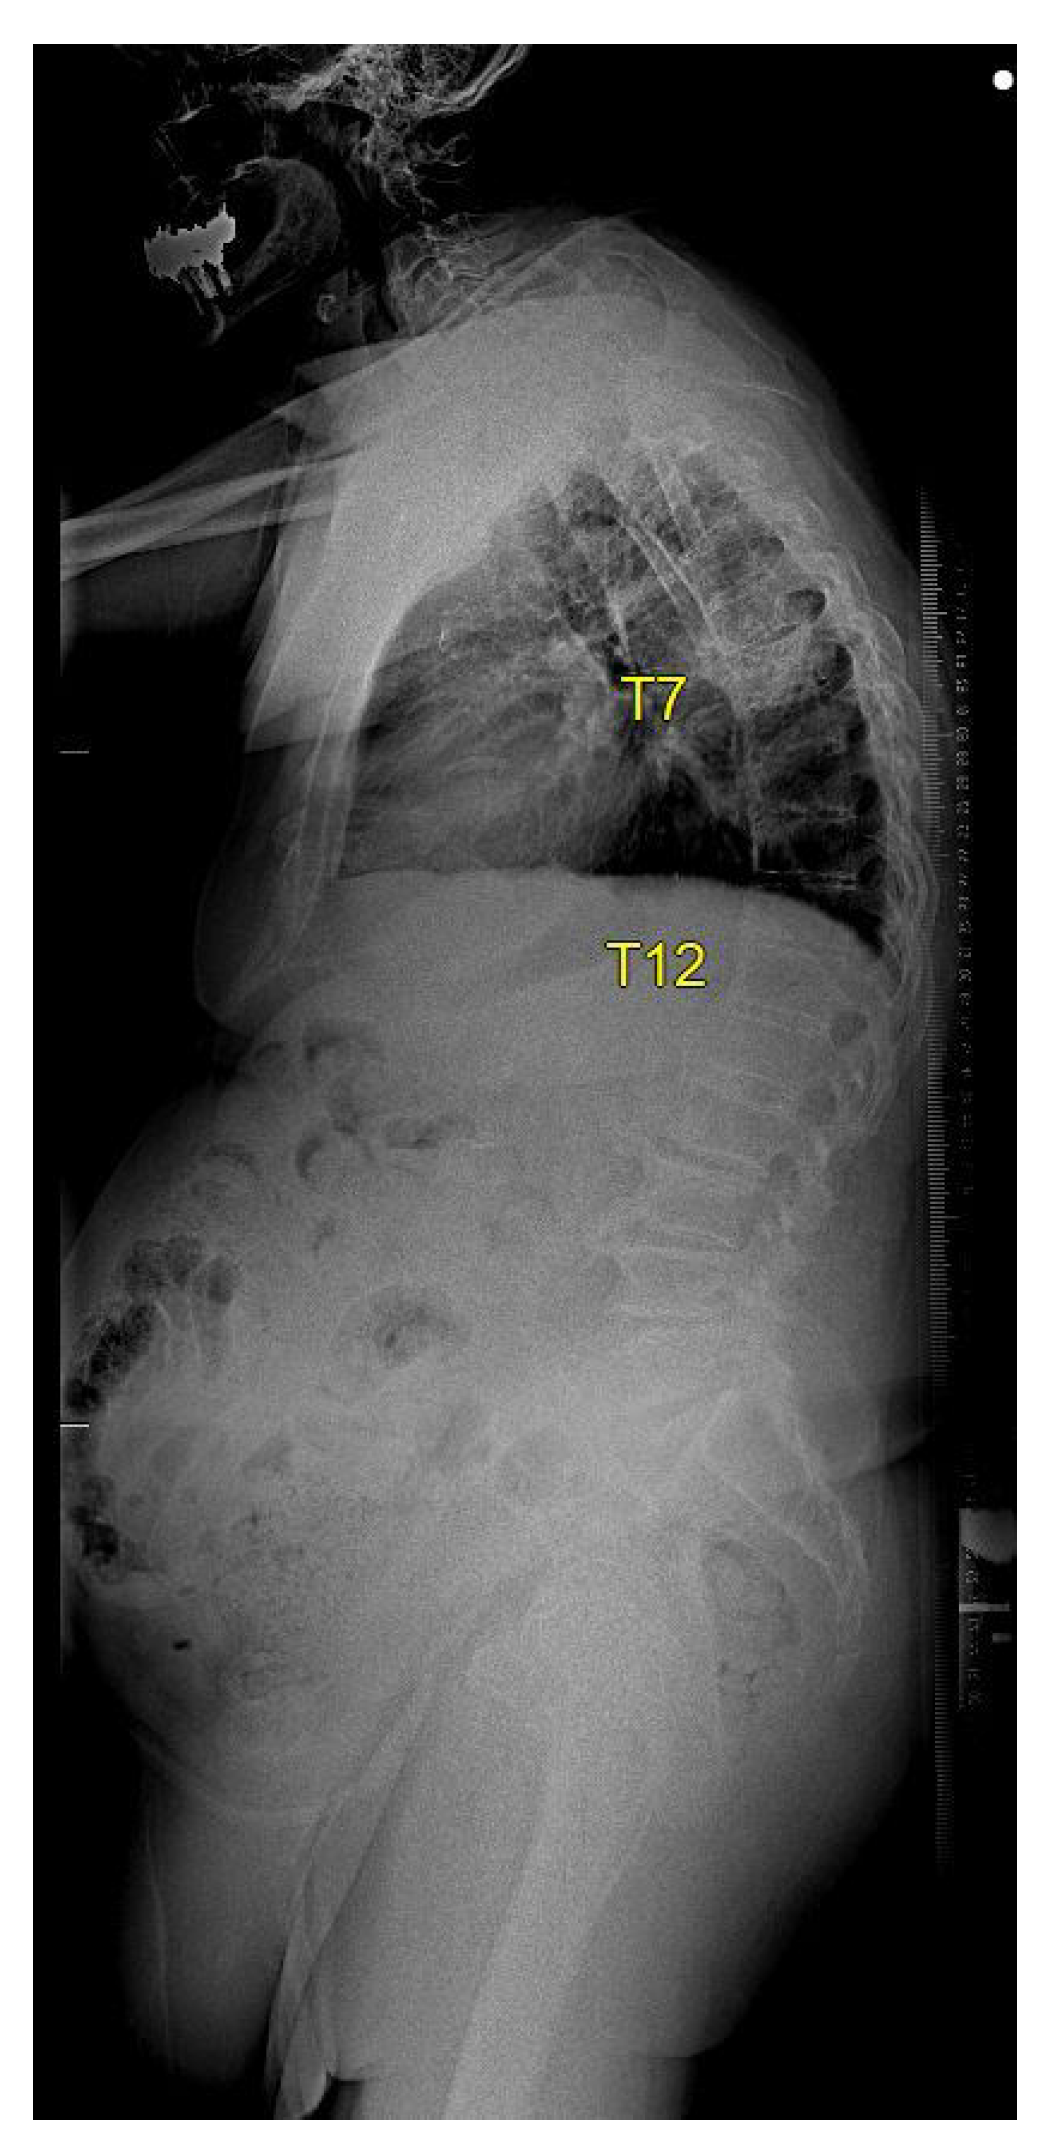

The case of an 81-year-old male, suffering from ischemic heart disease, atrial fibrillation, hypertension, morbid obesity, and gout, illustrates a unique treatment approach. He presented to the E.R. three days after a backward fall, having sustained an extension-type injury to T10–T11 a year and a half prior, which was treated non-operatively due to a very high operative risk. In the current fall, a new extension-type injury was identified at the T6–T7 level. He experienced back pain without radiating symptoms and had a long-standing foot drop but no new nerve deficit. His CT scans are shown in Figure A1. At a 4-month follow-up visit to the outpatient clinic, standing X-rays were performed, further confirming the stable healing of the fracture as shown in Figure A2.

Figure A2. Standing X-ray performed 4 months post-fracture, demonstrating solid fracture healing at T6–T7.